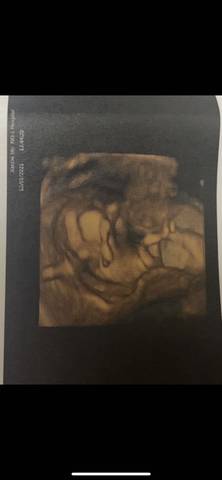

我这个应该是女宝吧哈哈哈好开心

你好。我们是判断不了男宝宝跟女宝宝的,孕期定期检查,我觉得宝宝健康就好的。祝心想事成 。

你好,对于宝宝是男孩女孩虽然很好奇,但是怀孕的单子、数据、表现是判断不出来的,在这也愿你心想事成。

看不出来,这个普通人是很难直接判断男孩还是女孩的哦,其实只要孩子健健康康就好,生下来才最准

你好根据B超单子是看不出男女的只要宝宝健康才是我们最大的心愿不是吗?最后祝宝妈心想事成哦。